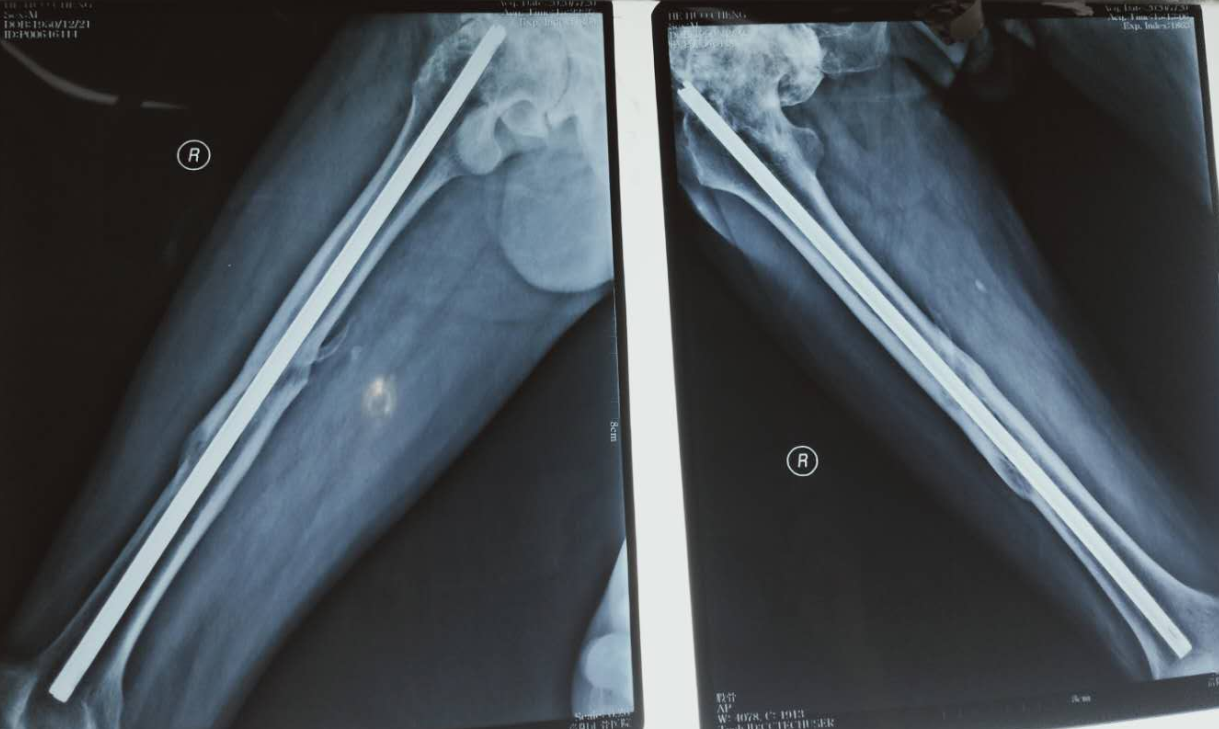

来自河南省博爱县的和先生已经69岁了,他于30年前的1989年10月份在开封某医院行右股骨骨折切开复位梅花形髓内钉内固定术,术后骨折愈合良好。由于家庭经济困难内固定物一直未取出。2年前患者出现右髋部疼痛,怀疑是髓内钉所致,于是到原医院要求取出内固定物,但原医院因不明原因未给予收治,之后辗转多家医院均以难以取出为由拒绝收治。无奈于2020年7月20日慕名前来我院白马寺院区求治。

入院后,综合骨二科主任刘威仔细检查,参照影像学检查分析,认为患者的右侧髋关节疼痛应该是股骨头坏死所致,髓内钉没有任何松动迹象,即向本人及家属讲明疼痛原因,并给予股骨头坏死的治疗方案,本人及家属坚决要求取出内固定物,并说明内固定物是他的一块心病。

为满足病人要求,刘威主任带领全科人员积极制定手术方案,发动全科人员寻找梅花形髓内钉取出器,刘威主任深知梅花形髓内钉是半封闭型,骨长入非常严重,没有配套的工具很难取出,王红超医师费尽周折,终于找到一副梅花形髓内钉取出器。

7月23日上午9时30分,和先生的取内固定术正式开始,正如预料的一样,取出过程异常艰难,滑动锤怎样滑动,髓内钉纹丝不动,用虎头钳夹着打,结果打断虎头钳一把。经过一个小时的努力,终于将这枚在人体内住了30年的梅花形髓内钉取出。病人千恩万谢,说:“刘主任团队解除了我30多年的心病,非常感谢!”